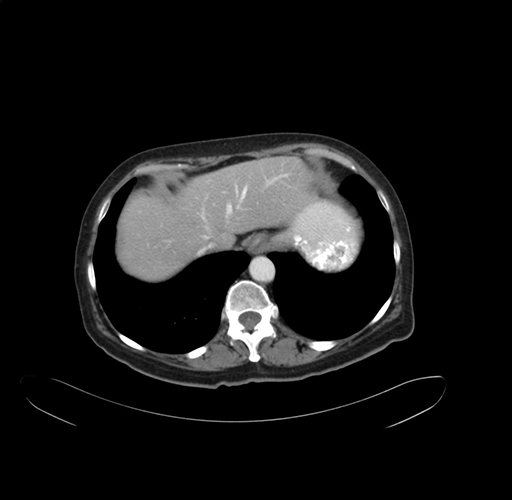

Pre-Chemo: Axial Venous